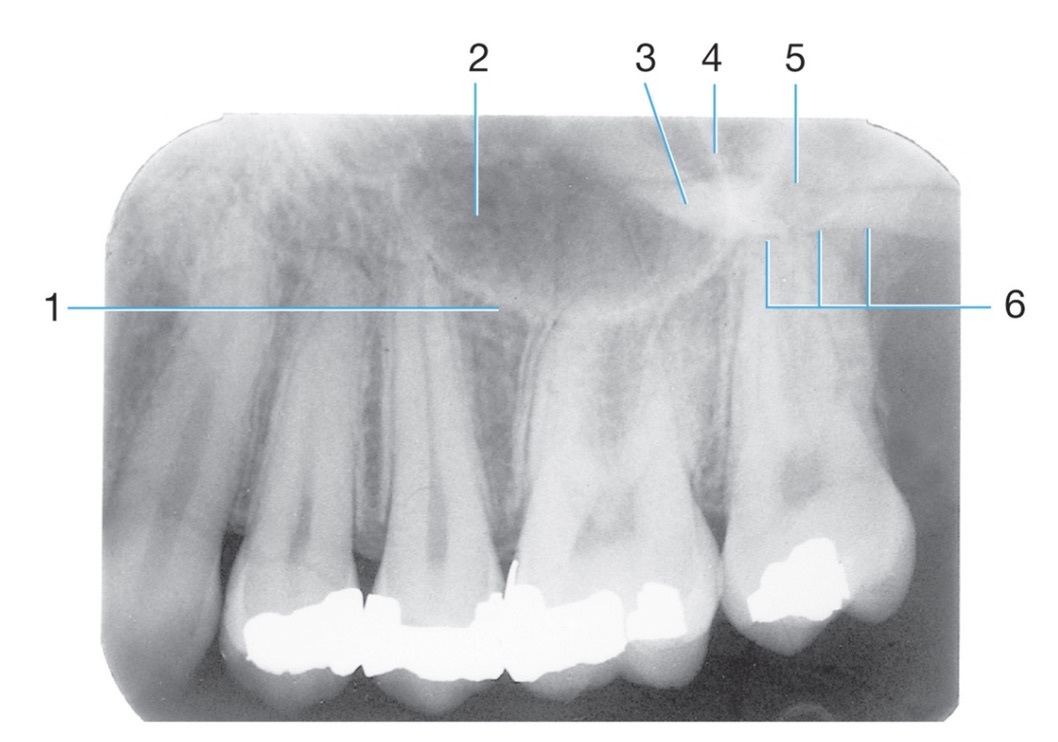

Identify #1.

Border of maxillary sinus

Identify #5.

Lateral pterygoid

Identify the air space image #2

nasopharyngeal

Intersection of the maxillary sinus & the nasal cavity

as viewed on a dental radiograph.

Inverted Y

J or U shape located above the maxillary first molars.

Radiolucent/Radiopaque?

zygomatic process of maxilla #4

Radiopaque

Name the classification of dental caries illustrated by 3

C-3 Advanced Caries

Advanced: Lesion that extends to or through the DEJ but does not extend more than half the distance to the pulp

Identify #3.

Nutrient foramen

6.

Post and core